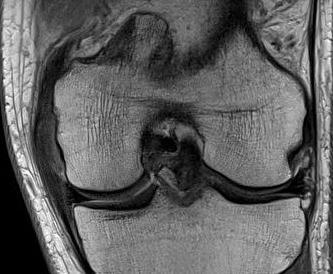

MRI

Classification

Grade I: intact ligament with periligamentous oedema

Grade II: partial tearing with surrounding oedema

Grade III: complete ligament tear

Sites

Femoral avulsion

Midsubstance

Tibial side: wave sign, ensure that the MCL is no flipped above pes anserinus as will not heal (analogous to Stener lesion)

Acute femoral avulsion

Midsubstance MCL tears

Wave sign indicative of tibial avulsion, with ligament retracted above pes anserinus / hamstring tendons

In the chronic setting see thickening of the MCL